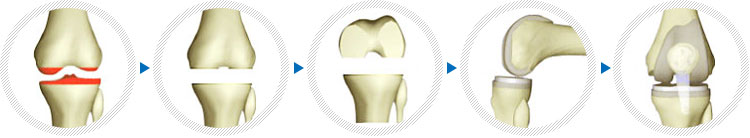

진행단계

인공슬관절 치환술은 무릎관절이 각종질환이나 외상 등의 원인으로 인해서 정상적인 일상 생활을 하지 못하고 장애가 심하면서 약물요법이나 물리치료 등에 치료가 불가능한 경우, 인공관절을 삽입하여 통증을 감소시키고 무릎관절 운동이 가능해지면서 동시에 안정성을 얻고 변형을 교정하여 일상적인 생활이 가능하게 해주는 수술입니다.